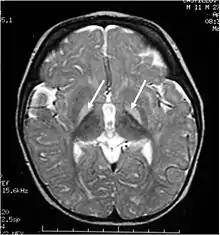

| Brain MRI. Hyperintense basal ganglia lesions on T2-weighted images. | |

These impairments are associated with lesions in the basal ganglia, auditory nuclei of the brain stem, and oculomotor nuclei of the brain stem. Cortex and white matter are subtly involved. Cerebellum may be involved. Severe cortical involvement is uncommon.